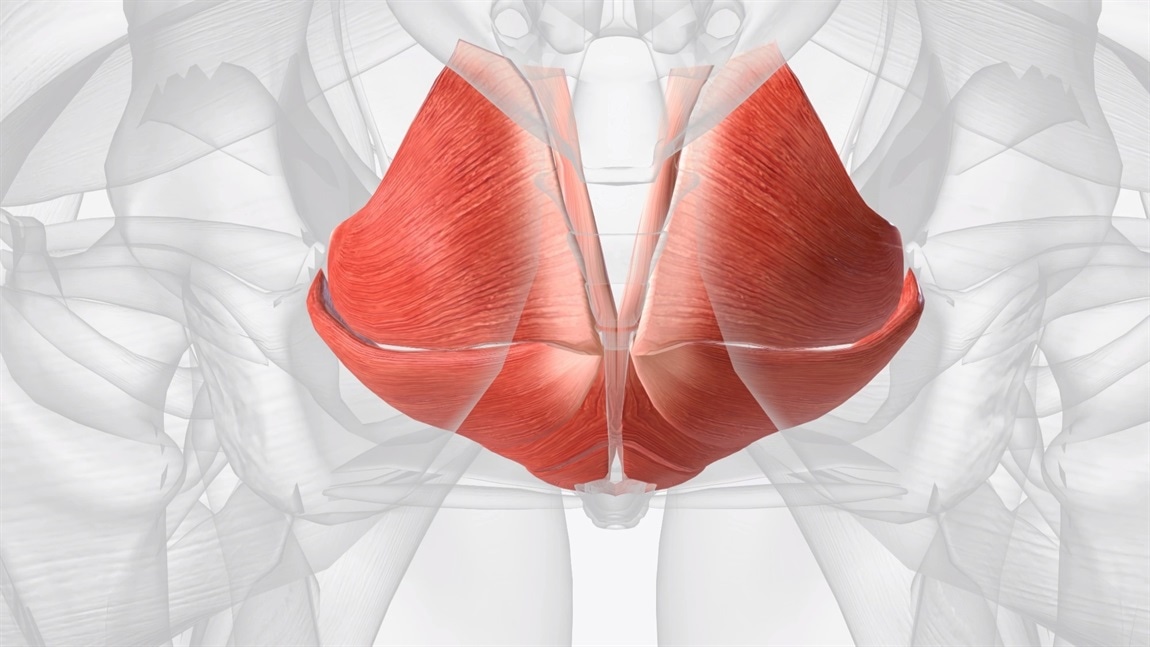

Leaking when you sneeze, cough, or laugh (called stress urinary incontinence) is experienced by a significant proportion of women in the postpartum period. A sense of pressure, heaviness, or dragging in the vaginal or perineal area (the area between the vagina and rectum) may indicate some degree of pelvic organ prolapse, a condition in which the bladder, uterus, or bowel descends into the vaginal canal due to weakened pelvic floor support. This does not mean a prolapse is severe or permanent. Mild prolapse is common postpartum, often resolves with targeted rehabilitation, and does not invariably require surgical intervention.

What is less discussed is the way the pelvic floor can also present as overly tight or hypertonic after birth, particularly in women who experienced a long or difficult second stage of labour, or who have significant perineal trauma. Pelvic floor hypertonicity (excessive muscle tension rather than weakness) can cause pain with penetration, difficulty inserting a tampon, pelvic heaviness, and incomplete bladder emptying. These symptoms are frequently misattributed to scar tissue, healing tenderness, or simply “being early in recovery,” when in fact they reflect a pelvic floor that needs skilled release work rather than more strengthening exercises.

This distinction matters enormously, because prescribing Kegel exercises (pelvic floor contractions) to a hypertonic pelvic floor is roughly equivalent to telling someone with a muscle spasm to clench harder. It can make things worse, not better.

At six weeks, your pelvic floor is still healing. Connective tissue, fascia, and muscle fibres are in active repair. The relaxin hormone, which loosened your ligaments and pelvic joints during pregnancy to facilitate delivery, remains elevated during breastfeeding. This means your pelvic floor support system is still in a state of relative laxity, even as it is trying to rebuild strength.